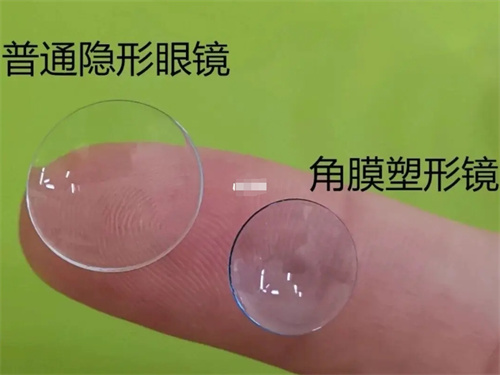

三焦点晶体:相比传统单焦点,可同时优化远、中、近视力,术后不用戴老花镜。

华视眼科是济南本地的老牌眼科机构,资质齐全,在三焦点晶体手术方面同样表现不错,尤其适合看重术后服务和性价比的家庭。

严格术前评估:确保患者符合手术条件,降低术后眩光等风险。